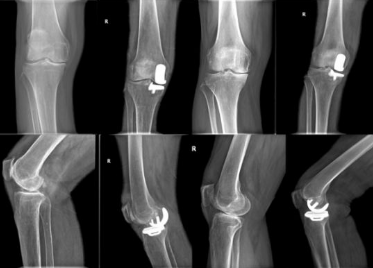

“以前听说膝骨关节炎需要手术做全膝关节置换,要不就长期吃药,没想到还能做微创,效果好还省了不少钱”患者彭女士(化名)说。

阅读次数:3960